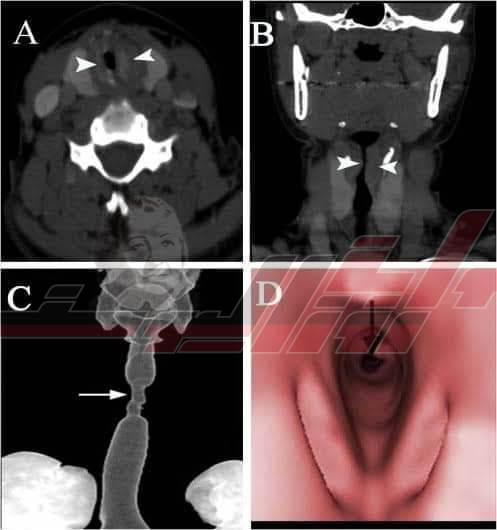

وفي خلال تلك الفترة توجه المريض للكشف عند أطباء الأمراض الصدرية والذين نصحوه بالتوجه لأطباء الأنف والأذن لأن السبب قد يكون ضيق بالحنجرة، وبالفحص وعمل أشعة مقطعية وتصوير للقصبة الهوائية تبين وجود ضيق شديد أسفل لسان المزمار، بسبب الأنبوبة الحنجرية وهي من المضاعفات المشهورة للعناية المركزة.

تم تجهيز المريض لإجراء جراحة منظار عاجلة الآن لتوسيع القصبة الهوائية مستشفيات بنها الجامعية، حيث تم التحدث مع الحالة لتوضيح أثر الأنبوبة الحنجرية في حالات العناية المركزة قبل وبعد المنظار، والذي يبين الفرق الشديد في الصوت والتحسن الواضح بعد المنظار.